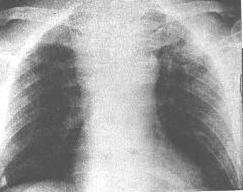

1.縱隔向兩側均勻增寬,見於大量出血。少量出血可無異常影像表現。2.局限性血腫表現為縱隔一側或兩側凸出的軟組織腫塊影,也可壓迫氣管或食管。

3.CT見瀰漫性出血表現為縱隔增寬,呈斑片狀或點狀密度不規則增高影。限局性血腫時密度均勻,邊緣清楚,CT值與主動脈相近。